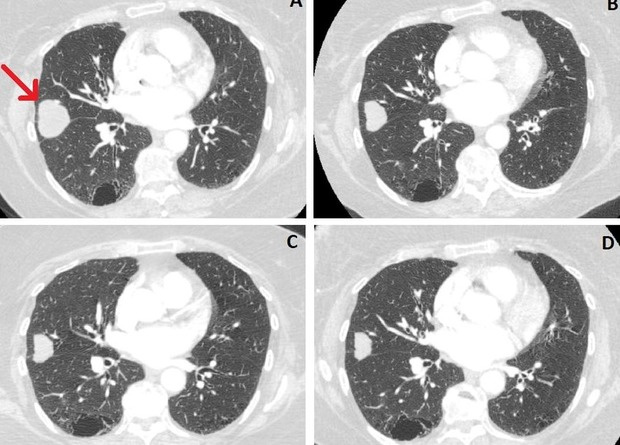

Британские врачи описали случай регресса злокачественной опухоли легкого у 80-летней женщины, который они связали с употреблением каннабидиола. Пациентка отказалась от операции и втайне от врачей принимала каннабиоид. Через 2,5 года размер опухоли легкого у нее уменьшился на 76 процентов. При этом другие медики настроены скептически: они считают, что регресс опухоли мог быть самопроизвольным и никак не связан с приемом каннабидиола. Случай описан в BMJ Case Reports.